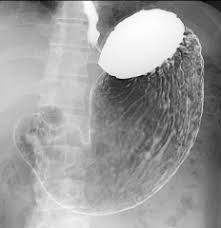

DAY SURGERY 日帰りポリープ手術

当院は「日帰り手術大腸ポリープ」を行っています。

例えば、大腸内視鏡検査を行った際に大腸ポリープが見つかり、切除が必要と判断すれば、その日のうちに切除を行うことも可能です。